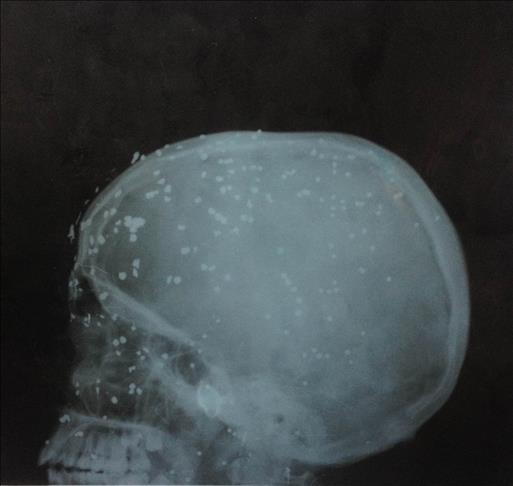

Now, he is a wounded boy lying on a hospital bed in Srinagar, Indian-held Kashmir's capital, with more than a hundred little iron balls embedded in his head.

The iron balls are described by Indian police as pellets and were shot from close range with a "non-lethal" gun. Several of them hit around his eyes.

Nazir’s X-ray reveals more than a 100 pellets lodged in his face, ears and head, and doctors say that some of them have also penetrated into his brain tissue.